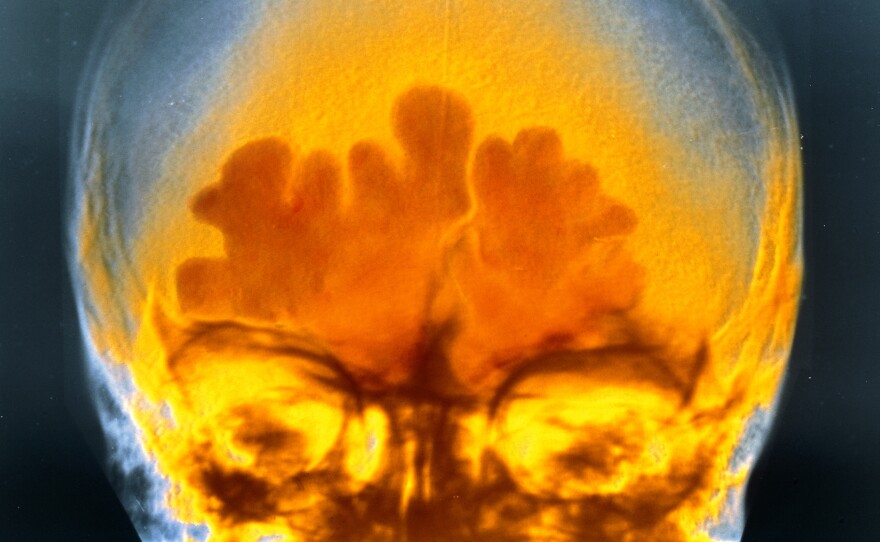

This is what the inflammation of sinus infection looks like in a false-color X-ray. It hurts even more in real life.